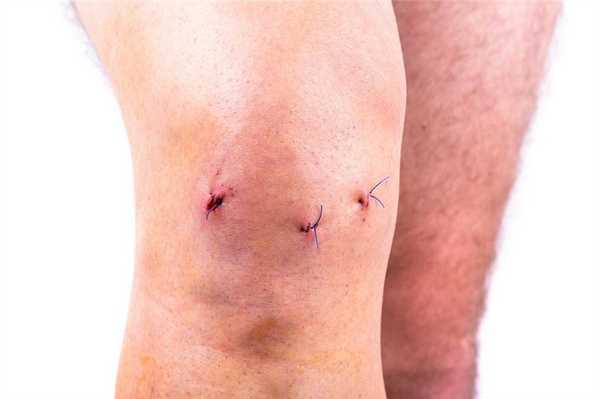

Операционные раны после артроскопии коленного сустава.

Когда снимают операционные швы?

Швы на колене после операции снимают обычно на 10 сутки. За это время должно произойти окончательное сращение краев раны, зафиксированных хирургическими нитями. Если разрез незначительный и быстро зажил, вам снимут швы на 7-й день. Вообще способность к регенерации мягких тканей, которые были рассечены в момент операции, у всех людей разная. У пожилой категории пациентов или людей, страдающих диабетом, окончательное заживление может состояться только на 12-14 день.

Судя по шрамам у данного пациента не левом коленном суставе была проведена частичная замена и артроскопия. Швы выглядят хорошо.